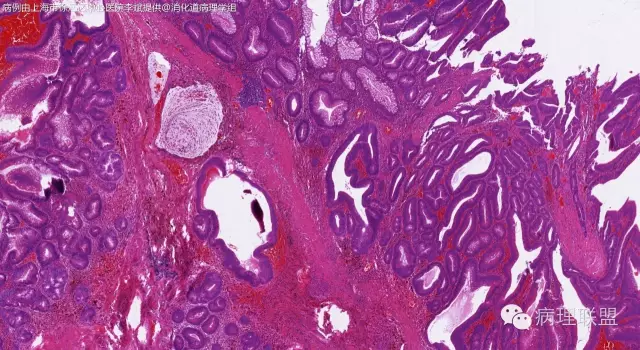

男,64岁,距肛门口45cm息肉大体:灰白结节2*2*1cm(病例由上海市徐汇区中心医院 李斌 提供,致谢!)

管状~绒毛状腺瘤伴低级别上皮内瘤变,黏膜下层部分腺体破裂黏液外溢伴黏液糊形成。

本例部分腺体异位到黏膜下层。

@李斌 李大夫的片子一向漂亮,有赏心悦目的感觉,必须赞一个。这例同意周大夫的意见,低级别绒毛管状腺瘤伴腺体破裂导致的黏液外溢。粘液池周围可见血管扩张淤血、含铁血黄素沉积、肉芽组织形成,提示发生过蒂扭转和出血,这常是造成假浸润、粘液溢出的原因。比较大的绒毛管状腺瘤会有分叶结构,会有比较粗大的平滑肌干,但缺少P-J息肉叶脉样从主干再分支出来的细平滑肌束。作为错构瘤性息肉的一种,P-J息肉的腺体可以分支、扩张、腺腔不规则,但没有细胞异型性,伴发异型增生时,局部出现细胞异型性但不会像这例这样齐刷刷都是异型的腺体。